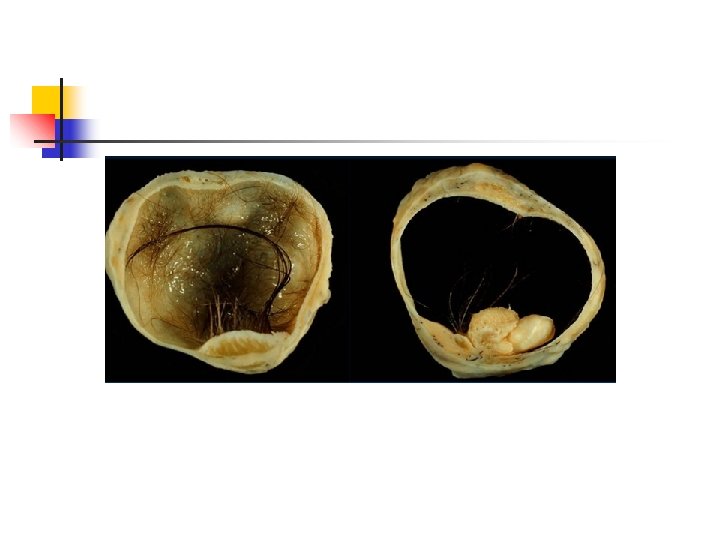

Dermoid Kist (Matur Kistik Teratom) Üç germ yaprağından matür dokular içerir. Ektoderm: cilt, kıl folikülü, sebase gland, nöral doku vb. Endoderm: akciğer, GİS dokusu vb. Mezoderm: kas, kemik, üriner sistem vb. 2. ve 3. dekattaki en sık over tümörüdür. Tüm over tümörlerinin %20’si, germ hücreli over tümörlerinin %95’inden fazlasını oluşturur. %10 -15 bilateraldir.

usg Karakteristik USG bulgusu kistik uniloküler kitle ve içerisinde dens ekojenik tüberkül( Rokitasky nodülü yada dermoid plak) olmasıdır. Multani 2015, Saba 2009